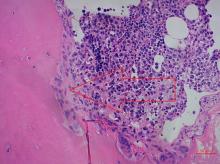

Multiplā mieloma ir salīdzinoši reti sastopama slimība, kas veido aptuveni 1 % no visiem onkoloģiskajiem saslimšanas gadījumiem un 13 % no visiem hematoloģiskajiem audzējiem. Pēdējos gados pieaugusi saslimstība ar šo ļaundabīgo neoplāziju gan Eiropā, gan Latvijā.

Multiplās mielomas diagnostikā izmanto vairākus testus: seroloģiskos, radioloģiskos, citoloģiskos, patohistoloģiskos un laboratoriskos, kas ārstiem ne tikai palīdz diagnosticēt multiplo mielomu, bet arī noteikt ārstēšanas taktiku un efektivitāti.